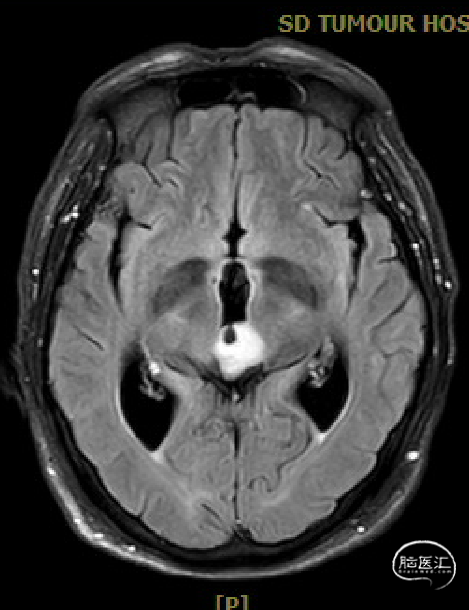

患者5年前无明显诱因出现阵发性头晕,无明显头痛、恶心呕吐等不适,开始未予重视,2022-7-19出现头晕加重,伴视力下降,遂于2022-7-24在当地医院行颅脑MRI提示:松果体区肿瘤伴梗阻性脑积水。

于该院在2022-7-27全麻下行松果体区病灶部分切除活检+神经内镜下第三脑室底造瘘术,术后由于取出肿瘤组织少,未能明确病理结果。患者术后恢复顺利,为进一步治疗就诊于我院。

松果体区占位,胶质瘤?生殖细胞肿瘤?